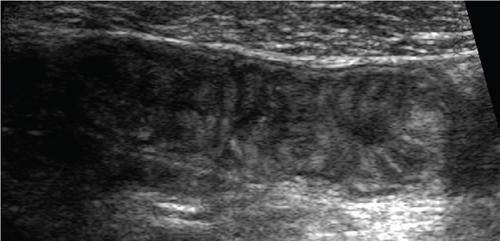

Ultrasonography in small bowel imaging